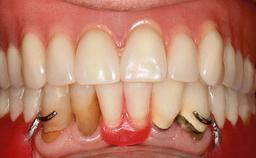

Improving an Existing Implant-supported Denture in an Alzheimer Patient with Bipolar Affective Disorder with Moderate Depression and Dementia

An 83-year-old man presented together with his caregiver at the dental department of the Medical University of Innsbruck, Austria with complaints of swelling in the right maxillary canine area and loss of retention of his 5-years-old mandibular denture. The patient had a significant medical history (20 years) of bipolar affective disorder with moderate depression (F 31.3) and dementia in Alzheimer’s disease (F 00.2). The patient had been in ambulant psychiatric therapy for his depressive illness for the past 20 years. He lived alone and had no children; his sister assisted with daily living. She reported that the patient exhibited compulsive hoarding behavior. In the previous two months, she had noted increasing disorientation and vertigo in the patient. She therefore accompanied him for a medical consultation at the Department of Psychiatry and Psychotherapy of the Medical University of Innsbruck. He was released home after a 6-week inpatient stay.

Lip Line No exposure of papillae Exposure of papillae Full exposure of mucosa margin

Soft Tissue Anatomy Intact Defective